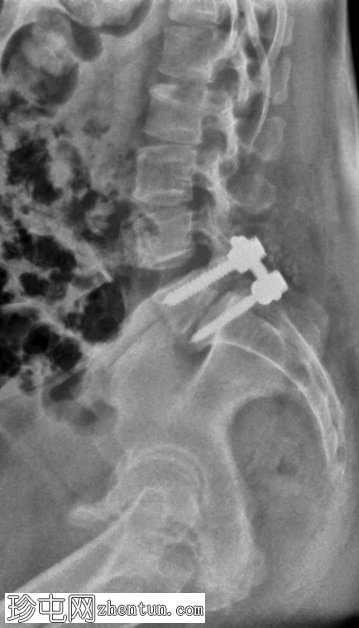

术后

X光片

7.png

侧面

L5和S1节段间有脊柱内固定器械。

椎弓根螺钉和棒已置入。